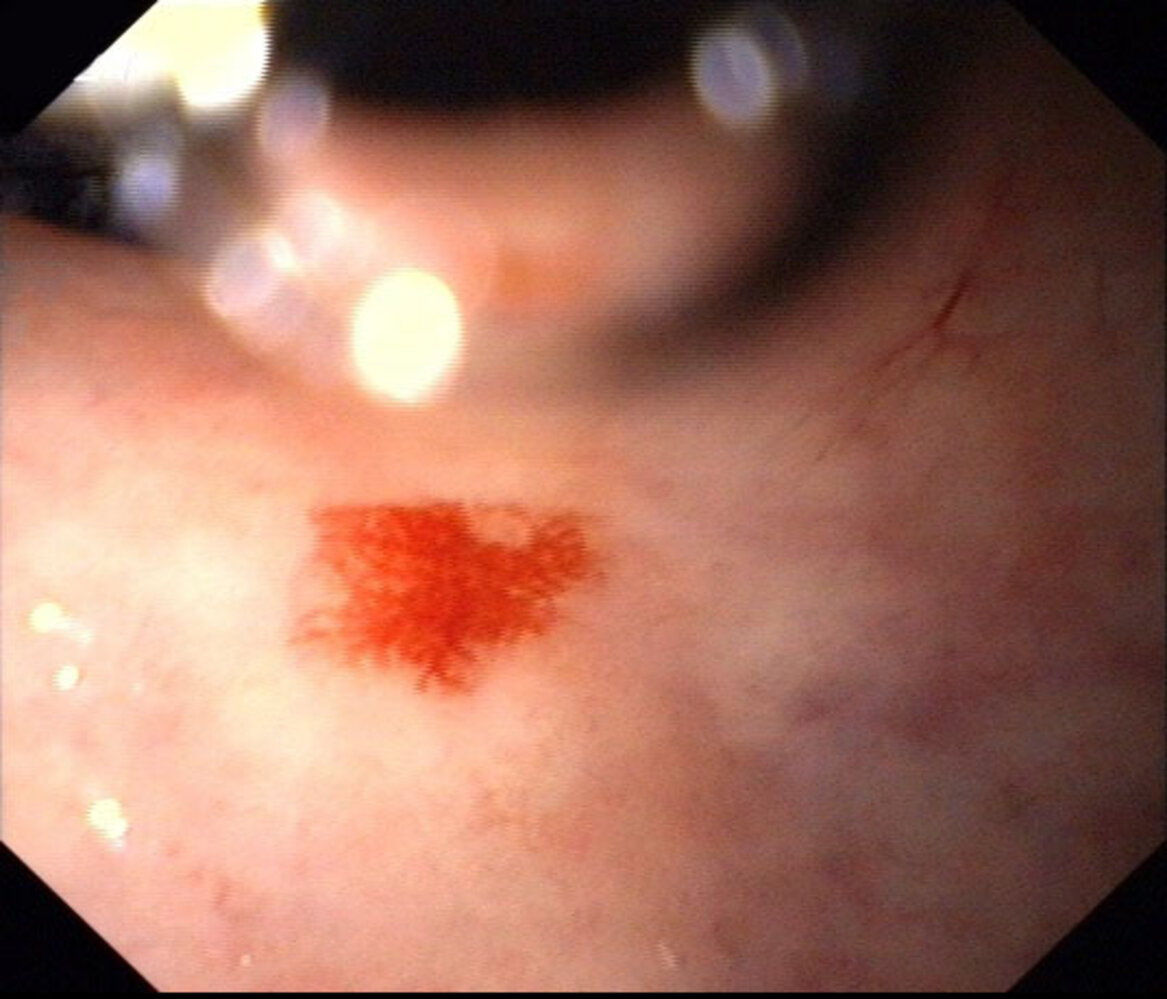

• Findings [2][3]

• Lesion characteristics

• Vessel: flat, cherry-red, and with a fern-like pattern

• Size: < 10 mm

• “Pale halo” sign: a ring of pale mucosa surrounding the angiodysplastic lesion